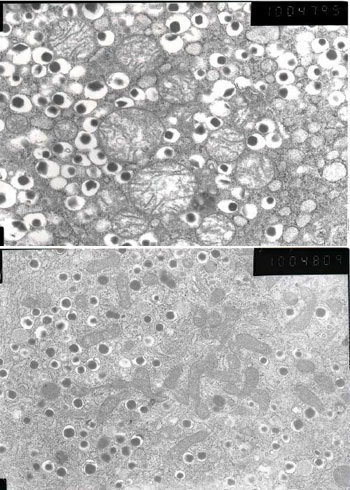

结果幼鼠出生时处于营养失调状态,体重比正常白鼠低20%左右。断奶后,即使喂以正常饲料,体重也不太容易增长。在出生20周之后,研究组分解了这只幼鼠的胰腺,通过电子显微镜进行了观察。出生20周的鼠,相当于20、30多岁的人。

观察结果显示,分泌胰岛素的β细胞明显变小,数量也少于正常白鼠。β细胞内的线粒体数量也有所减少,形状也非正常性地变得细长。研究组推测,这是由于因缺乏营养而出现问题的母鼠的线粒体遗传给了幼鼠。